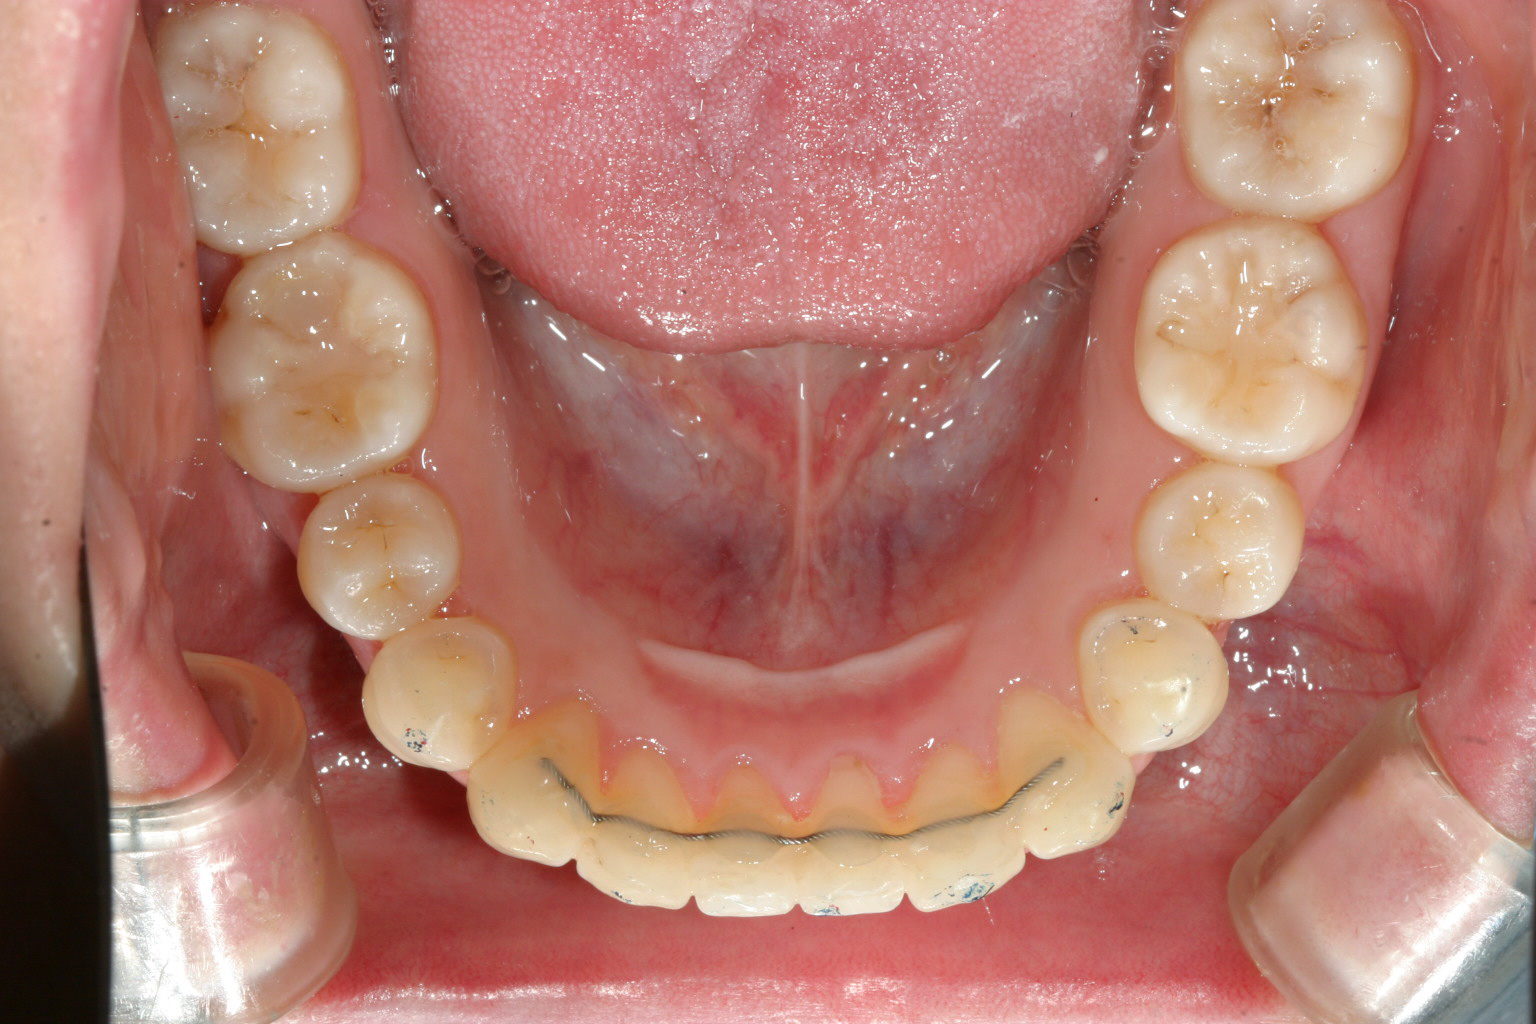

今回のケースはアーチの前歯部が狭い為に前歯が上手く並ばず飛び出した状態になっています。

当医院の症例の中でも一番頻度の高いケースでいつものようにアーチをU字に改善する事から始めます。

後はIPR(歯と歯の間を少し削る事)により上下の歯のかみ合わせバランスを整えます。

この様なケースは非常に多いですが現在の世の中加速矯正装置を使用しますと1年以内で、上手く行くと半年で改善します。

前歯は他人からも見え第一印象として大事ですからこの様な歯並びでお悩みでしたら一度相談にお越しください。